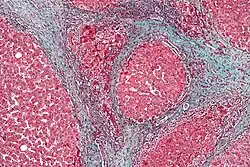

Replacement fibrosis in myocardial infarction, being boundless and dense.

Replacement fibrosis in myocardial infarction, being boundless and dense.